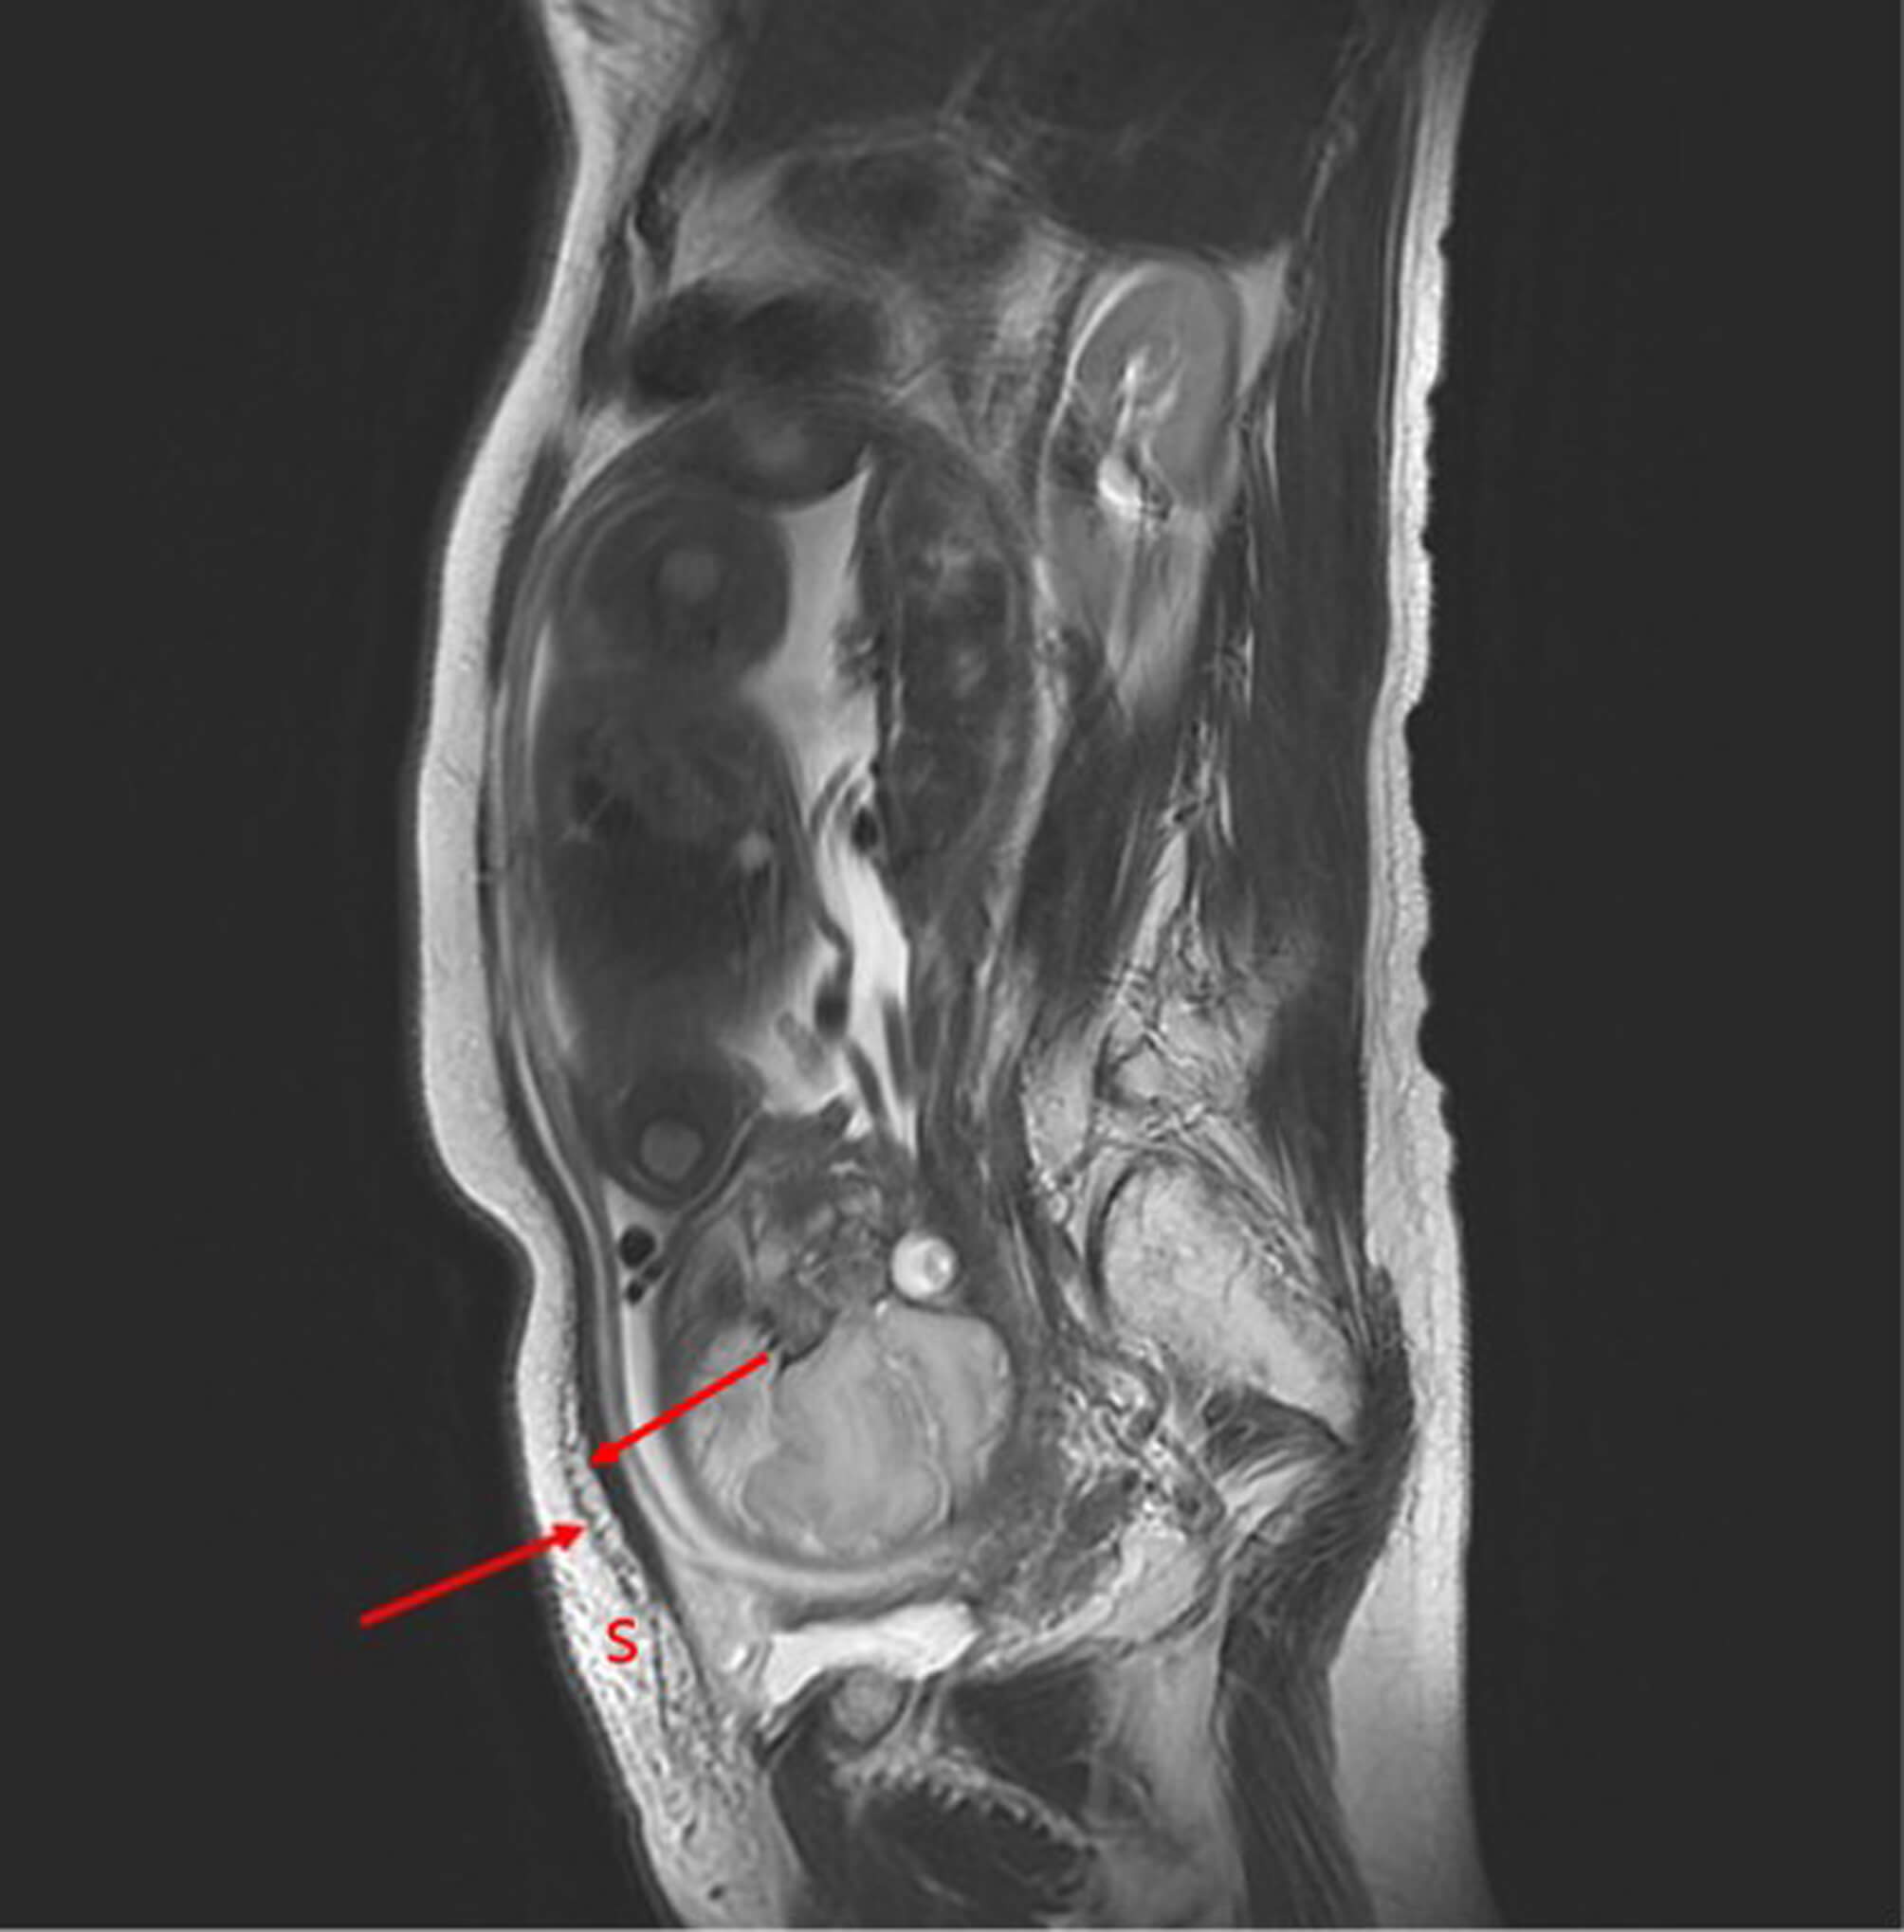

The patient underwent routine prenatal care, and placenta previa persisted, prompting a planned cesarean delivery. From 34 weeks’ gestation, she developed elevated blood pressure and proteinuria, consistent with preeclampsia. Cesarean delivery was scheduled to be performed at approximately 36 weeks of gestation. To assess filler distribution, its relationship with the abdominal wall, and the extent of placental invasion, pelvic magnetic resonance imaging (MRI) was performed. MRI revealed hyperechoic fluid collections containing small, round, bubble-like particles located between the subcutaneous tissue and the fascial layer of the abdominal wall (Fig. 2).

Fig. 2.

Sagittal non-enhanced pelvic MRI demonstrating abdominal wall fluid collection. Sagittal non-enhanced pelvic MRI revealed hyperintense fluid collections containing small, round, bubble-like particles located between the subcutaneous tissue and fascial layer of the abdominal wall (red arrow). S, subcutaneous tissue; MRI, magnetic resonance imaging.